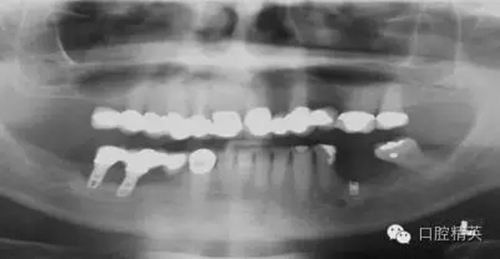

圖2a:術后曲面斷層片顯示兩顆種植體分別異位于左右側上頜竇中

另一個和醫(yī)生僅用兩維放射線檢查造成的特殊并發(fā)癥是種植體進入上頜竇。(圖2a-c)可能成為上頜竇異物的有牙齒,牙根,印模材料,牙科器械,近年來又增加了一個—種植體。可想而知,從上頜竇中取出異物對患者來講是創(chuàng)傷很大的。

其他研究也報道過,對于這種病例,唯一的選擇是用根管顯微鏡或Caldwell Luc技術從上頜竇中取出種植體。有些文章報道了如何處理進入上頜竇的種植體,但很少從預防的角度來談這個問題,其實很簡單,術前應該應用CBCT成像檢查。